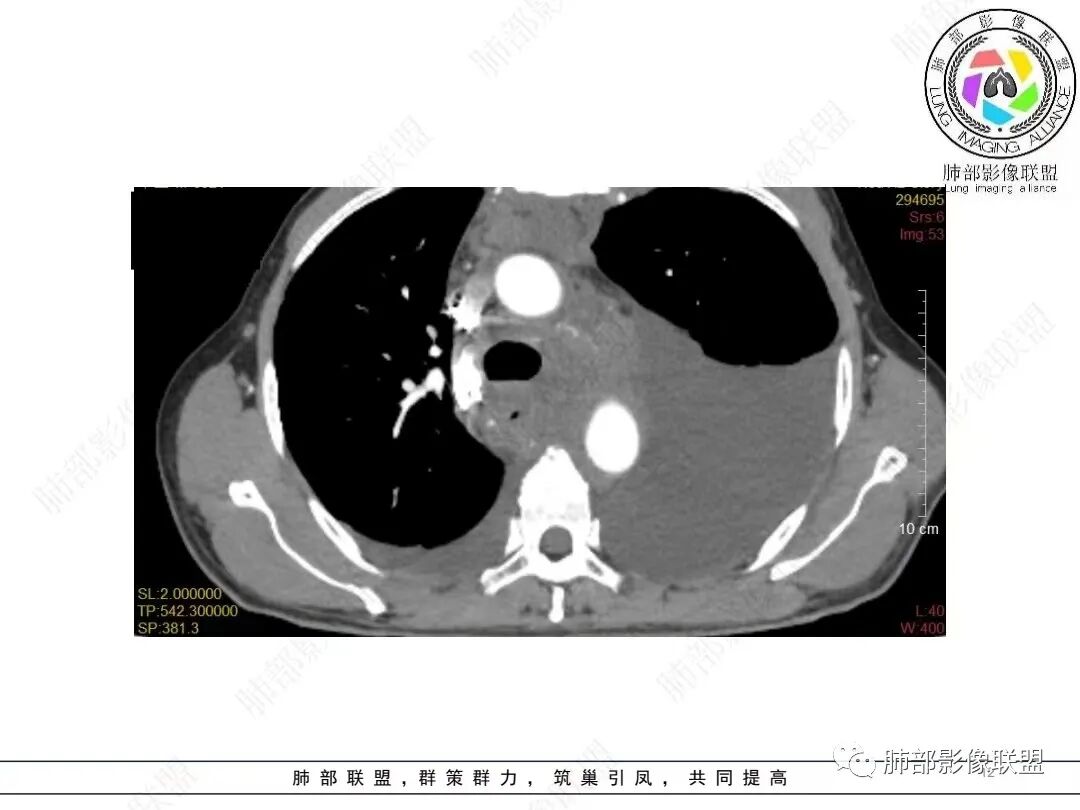

目前的图:主要是胸部的病灶。胸膜弥漫斑块状增厚。强化明显,内部血管漂浮。前纵隔部分病灶强化偏低。

累及多个腔隙、特别是后纵隔、胸膜为主

常规淋巴瘤、胸膜间皮瘤要警惕

2.影像学特点:病变范围相当广泛,多发块状影累及纵隔、胸膜、前胸壁(胸大肌下)、前上腹壁等。胸膜弥漫性斑状增厚为主,明显强化,纵隔旁椭圆形块影较密实,沿胸膜分布趋势,未见支气管等结构进入。后纵隔块影较大,占位效应明显,肺静脉受累狭窄。双侧胸腔积液。